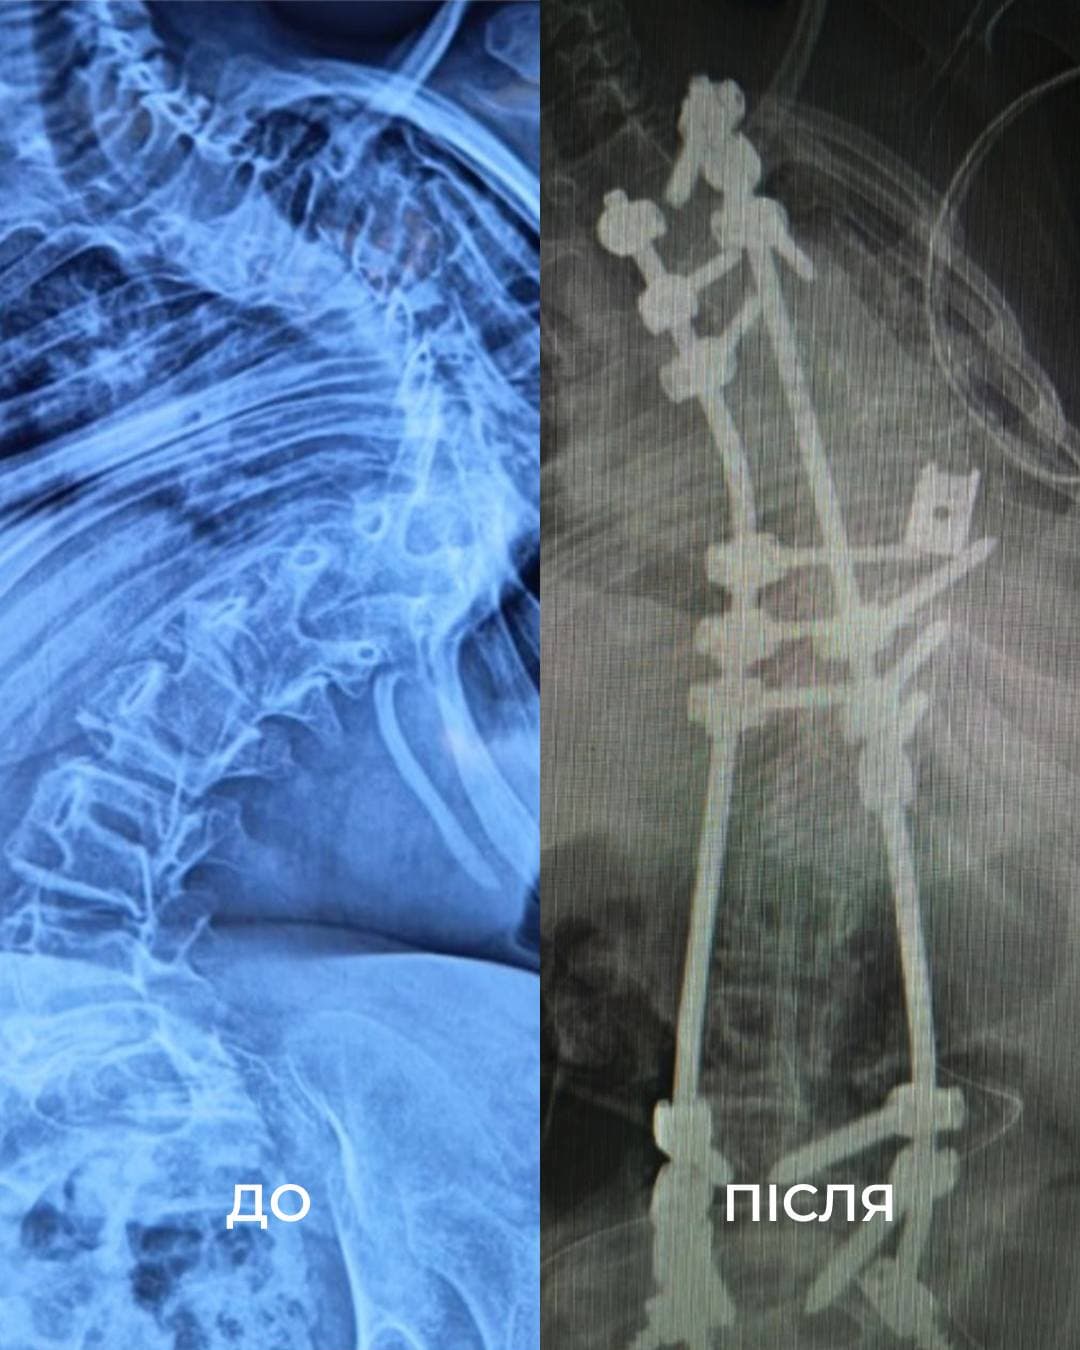

Як повідомили у Дитячій лікарні Святого Миколая, у дівчинки діагностували міопатію Бетлема — рідкісне генетичне захворювання, яке спричиняє слабкість м’язів і призводить до важкого сколіозу. З часом хребет Віки викривився на 160 градусів, що спричиняло сильний біль, задишку та обмеження рухливості.

«Щоб виправити її сколіоз, нам потрібно було видалити цілий хребець. У перший день операції ми закріпили її хребет гвинтами. А потім уже на другий день видалили кілька ребер, ізолювали спинний мозок та встановили титанову клітку для підтримки хребта. А потім повільно виправляли її разом з моєю колегою, нейрофізіологинею Меган Маллані», — розповідає американський ортопед-травматолог Марк Диржка.